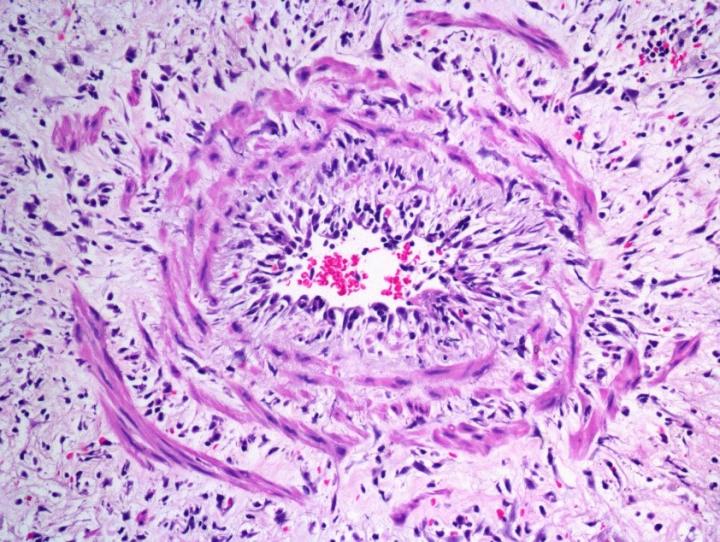

For years, doctors have observed that some patients with leprosy develop unusual blood clots which can lead to stroke or heart attack. Now, researchers reporting in PLOS Neglected Tropical Diseases have for the first time characterized these blood clots, leading to a new understanding of how leprosy affects the circulatory system and potential new screening tests to predict leprosy reactions.

Flavio Alves Lara of the Oswaldo Cruz Institute, and colleagues searched for blood clotting abnormalities among 638 leprosy patients and identified 35 patients who had unusual fatty clots, which the researchers dubbed "leprosum clots." The team went on to study what factors predicted the development of leprosum clots and what molecules were present in the clots.

The researchers found that patients both experiencing a reactional episode and those with non-reactional leprosy had factors in their blood--including plasmatic fibrinogen, anti-cardiolipin antibodies, von Willebrand factor, and soluble tissue factor-- promoting blood coagulation. Formation of leprosum clots, they showed, was correlated with increased levels of soluble tissue factor and von Willebrand factor. Tests on leprosum clots revealed high contents of lipids and fibrinogen, and showed higher levels of two proteins--complement component 3 and 4 and inter-alpha- trypsin inhibitor family heavy chain-related protein (IHRP)--compared to clots from patients without leprosy.